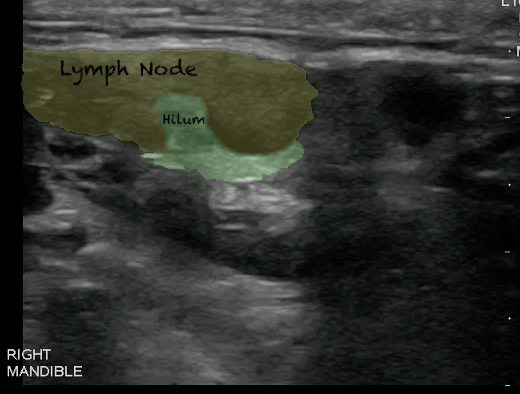

- Videos 7 and 8. Lymph nodes

- Normal lymph node

- Oval in appearance

- Echogenic hilum

- Homogenous in echotexture

- Doppler blood flow is seen branching radially from the hilum and no flow is seen in the periphery

Video 9. Color doppler on lymph node

- Figures 11 and 12. Lymph Node